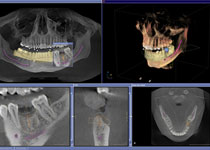

High-Tech Röntgen in 3D: Präzise, sicher, schonend und schnell!

Der Wunsch vieler Patienten/Innen ist es beim Röntgen nicht den starken Strahlen ausgesetzt zu sein. Diesem Wunsch können wir Folge leisten, denn mit unserem 3D Röntgengerät ORTHOPHOS XG 3D von Sirona bieten wir unseren Patienten eine geringere Strahlenbelastung als bei herkömmlichen Röntgenaufnahmen. Es ist keine Überweisung an Kollegen oder Röntgeninstitute mehr notwendig, um extern die Röntgenaufnahmen erstellen zu lassen. Alles findet in unserem Hause statt.

High-Tech Röntgen in 3D: Wer mehr sieht kann besser behandeln!

Dr. Poll und Dr. Gorden von der Gemeinschaftspraxis für Zahn-, Mund- und Kieferheilkunde in Dortmund freuen sich: Das neue 3D Röntgengerät ORTHOPHOS XG 3D von Sirona ist eingetroffen und optimiert, wo nötig, alle Behandlungsabläufe! Das Gerät verfügt über modernste 3-D-Röntgentechnologie. Damit ist es möglich, mit nur einem Scan den gesamten Kiefer des Patienten zu erfassen. Die geringere Strahlenbelastung ist dabei ebenso für Sie von Vorteil wie die Zeitersparnis...